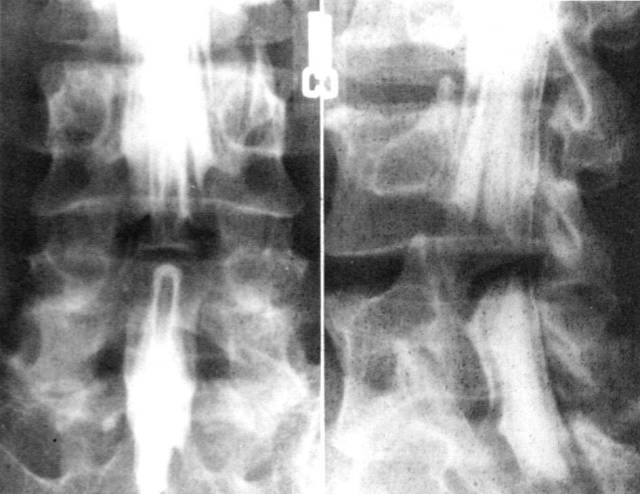

2、椎管造影:椎管造影在诊断椎管狭窄症中有重要价值。能直接在荧光透视下动态观察造影剂在椎管内流动情况。显示椎管、硬膜囊、神经根袖全貌。

但椎管造影为有创性检查,患者不易接受。侧隐窝病变不能清晰显示,不能显示椎管横断面骨和神经根形态。

腰椎管狭窄者椎管造影均有不同程度的造影剂充盈缺损。完全梗阻断处常呈幕帘状、笔尖状,弹头状样充盈缺损。不完全梗阻断处常呈点滴状通过,其结果呈葫芦状、哑铃状或灯笼状等。

前屈后伸位造影对比

椎管造影

中央型椎管狭窄突出

造影斜位可清晰显示神经根袖